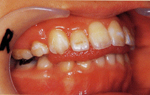

7 歳女子・叢生(乱杭歯)

叢生(乱杭歯)   叢生(乱杭歯)   叢生(乱杭歯)

治療後2年後